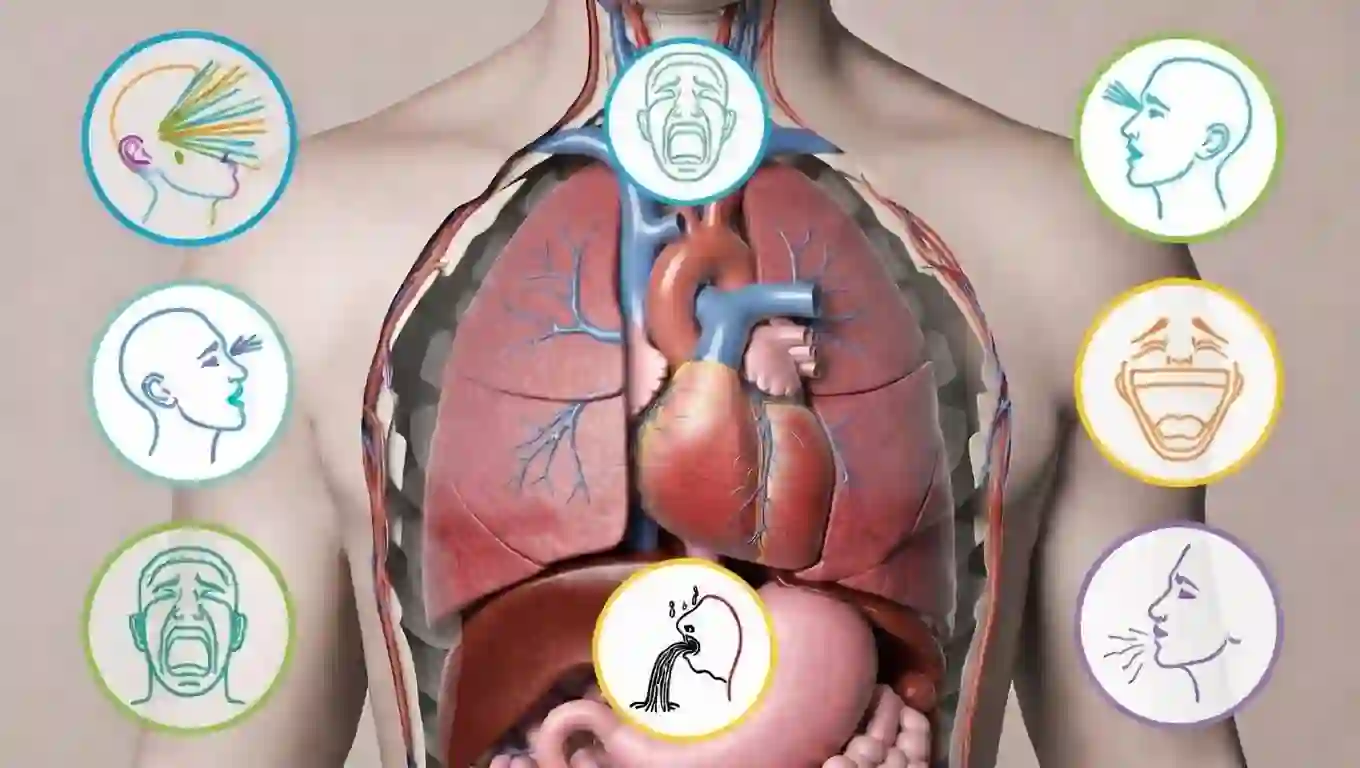

🌬️ یکی از شایعترین علائم نارسایی قلبی تنگی نفس است. بیمار ممکن است هنگام فعالیت، دراز کشیدن یا حتی در حالت استراحت احساس کمبود هوا کند. این تنگی نفس بهدلیل تجمع مایع در ریهها رخ میدهد و میتواند بسیار آزاردهنده باشد.

🧠 خستگی زودرس یکی دیگر از علائم مهم نارسایی قلبی است. وقتی قلب نتواند خون کافی به عضلات برساند، فرد حتی با فعالیتهای ساده احساس ضعف میکند. این خستگی معمولاً بهتدریج ایجاد میشود و ممکن است در ابتدا نادیده گرفته شود.

🦵 ورم پاها و مچها از نشانههای رایج نارسایی قلبی است. این ورم بهدلیل تجمع مایع در بافتها ایجاد میشود و معمولاً در پایان روز بیشتر است. در موارد شدید، ورم ممکن است به شکم نیز گسترش یابد.

🫁 سرفههای شبانه یا احساس خفگی هنگام خواب میتواند نشانه نارسایی قلبی باشد. این حالت بهدلیل برگشت مایع به ریهها در حالت درازکش رخ میدهد و ممکن است بیمار را از خواب بیدار کند.